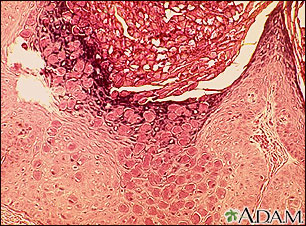

This is how a molluscum lesion appears under microscopic examination. Molluscum are small, raised, pearly skin lesions caused by the molluscum virus, a member of the poxvirus family.